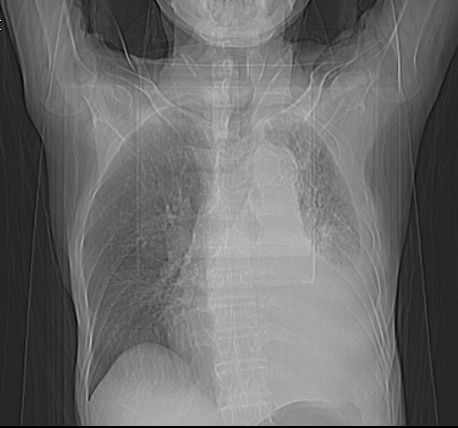

标题: CT10141:男、84岁,咳嗽、咯血1年。 [打印本页]

标题: CT10141:男、84岁,咳嗽、咯血1年。

1左侧胸腔积液并包裹2心包积液3左下肺癌?建议支纤镜检。

支持左侧中央型肺癌伴下叶肺不张\\纵隔淋巴结转移.左侧包裹性胸腔积液\\心包积液.左侧少量胸腔积液..慢性支气管炎伴部分间质纤维化.

左侧中心型肺癌,胖左侧胸腔积液

左肺中心性肺癌并肺不张,同侧 胸膜及心包转移,左肺癌性淋巴管炎

左侧中心型肺癌,左侧胸腔积液部分包裹,心包积液,肿膈淋巴结显示。

咯血病史较长,左肺下叶实变,体积未明显缩小,隐约可见血管影及坏死阴影,双肺门及纵隔淋巴结增大,心包增厚积液,纵隔右移位,单侧胸腔积液,首先考虑:大叶型肺泡癌伴纵隔心包转移。

左下中央型肺癌伴阻塞性不张,肺炎,左侧包裹性胸腔积液\\心包积液

左肺中心性肺癌并左肺下叶肺不张,纵隔淋巴转移、同侧胸腔及心包积液(转移)。